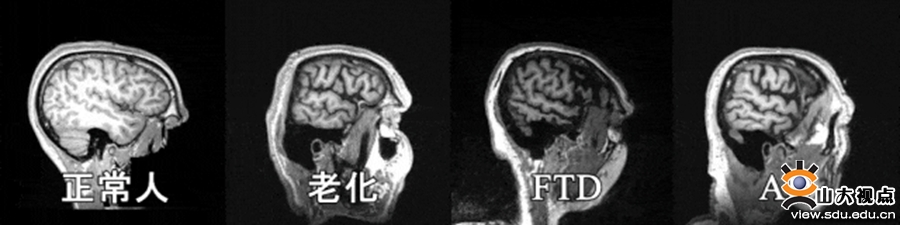

正常老化、阿尔茨海默病(AD)和额颞叶痴呆(FTD)等神经退行性疾病(或过程)具有的交叉重叠的脑结构表征,却具有典型区别的临床表现。“不同疾病(状态)之间的脑结构特异性表征是什么”“什么微观因素导致了不同疾病(状态)的复杂临床表型”是当前尚未解决的关键科学问题。

研究发现老化呈现分布广泛但程度轻微的脑结构变化,而AD则呈现出典型的区域损伤,如默认网络和皮下核团,揭示了通过复杂脑网络结构可以更好地捕捉疾病特异性表征。研究进一步探索了不同疾病脑结构异常模式背后潜在的生物机制,结果显示老化主要与离子运输变化相关,不同痴呆类疾病则与化学神经递质异常相关,揭示了痴呆与老化生物过程的差异。此外,研究还揭示了不同痴呆类型之间的特异性,如AD主要与5-羟色胺系统相关,帕金森(PD)主要与多巴胺系统相关,为不同类型痴呆的特异性临床表型提供了生物学依据,也为不同疾病提供潜在干预靶点。